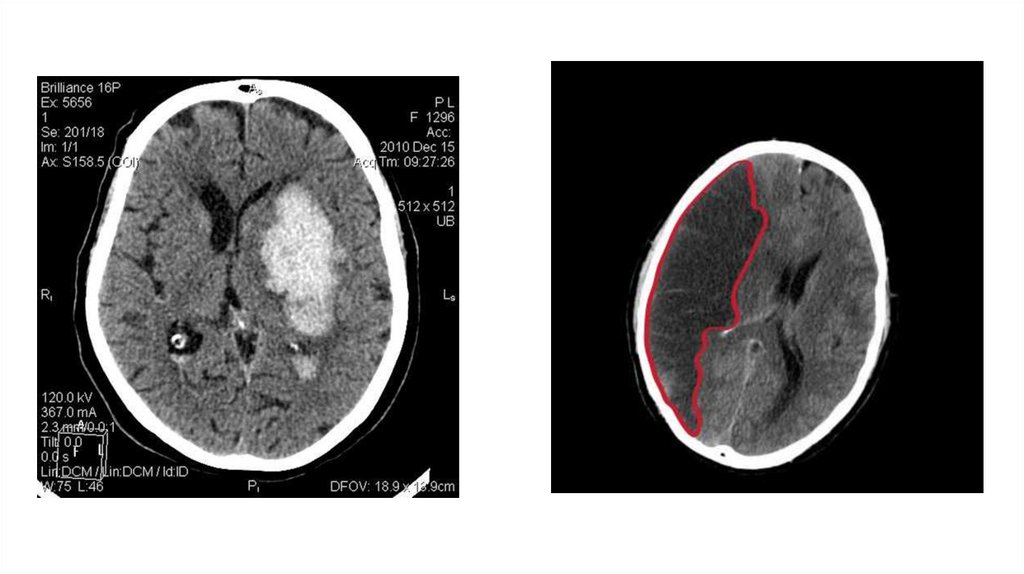

Ишемический инсульт на КТ